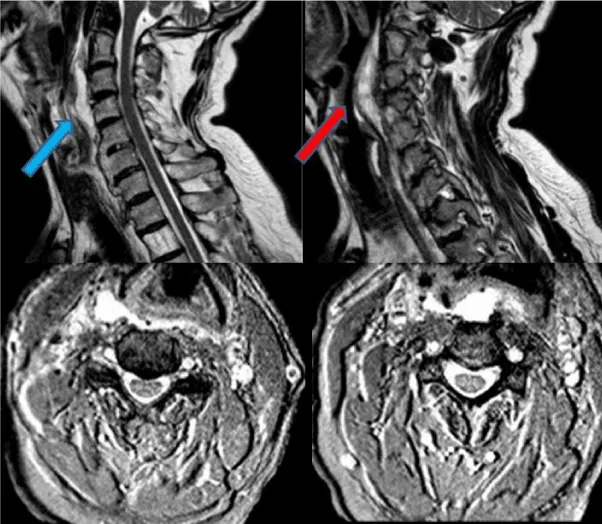

A 65- year old male patient with history of diabetes mellitus was admitted to our outpatient clinic with neck pain, dysphagia and sleep apnea for over 5 months. Previously evaluated by the otolaryngology department a esophagography a slight compression of the upper cervical esophagus segment was observed. He stated that he lost 6kg in 6months due to the dysphagia. On his cervical CT scan revealed broad ossification of the anterior longitudinal ligament from C2 to T1 with anteriorly beaking osteophytes surrounding the vertebral bodies causing compression of the trachea and esophagus on C2 and C3 (Figure 1). Magnetic Resonance Imaging (MRI) showed that there were no disc pathologies; vertebral heights and spinal alimentation were normal. The spinal canal and spinal cord were intact. (Figure 2). With the diagnosis of DISH, the patient underwent surgery. With an anterolateral approach the ossified pathological segment was removed with a high-speed drill and no compression of the surrounding soft tissue fractures were confirmed. The patient’s symptoms revealed immediately after the surgery and on the postoperative control CT scan, total clearance of the ossified structures were observed (Figure 3).

The fact that makes our case unique is the multiple cervical vertebra involvement of DISH starting in the upper cervical vertebra which has not been reported in the literature in this variety before. Forestier disease, being more common in the thoracic and lower cervical area, show a vertical growing pattern in the thoracic and horizontal pattern in the cervical area. In our patient the ossification mimicking a bird’s beak had vertical growing characteristics despite being in the upper cervical area. Also, multi-level involvement in the cervical spine is rare because the cervical vertebrae are more mobile than the ones in the thoracic area. In our patient ossification from C2 to T1 was present which has not been presented in the literature before. Rapid improvement of the patient’s symptoms confirmed with the radiological images strenghten the hypothesis that patients with dysphagia, especially in the ones with weight loss due to it, have better outcomes when approached surgically than conservatively. In our opinion, it is not necessary to remove all the ossificated levels. In our case, we just drilled the segment in contact with the esophagus and trachea and had excellent results.